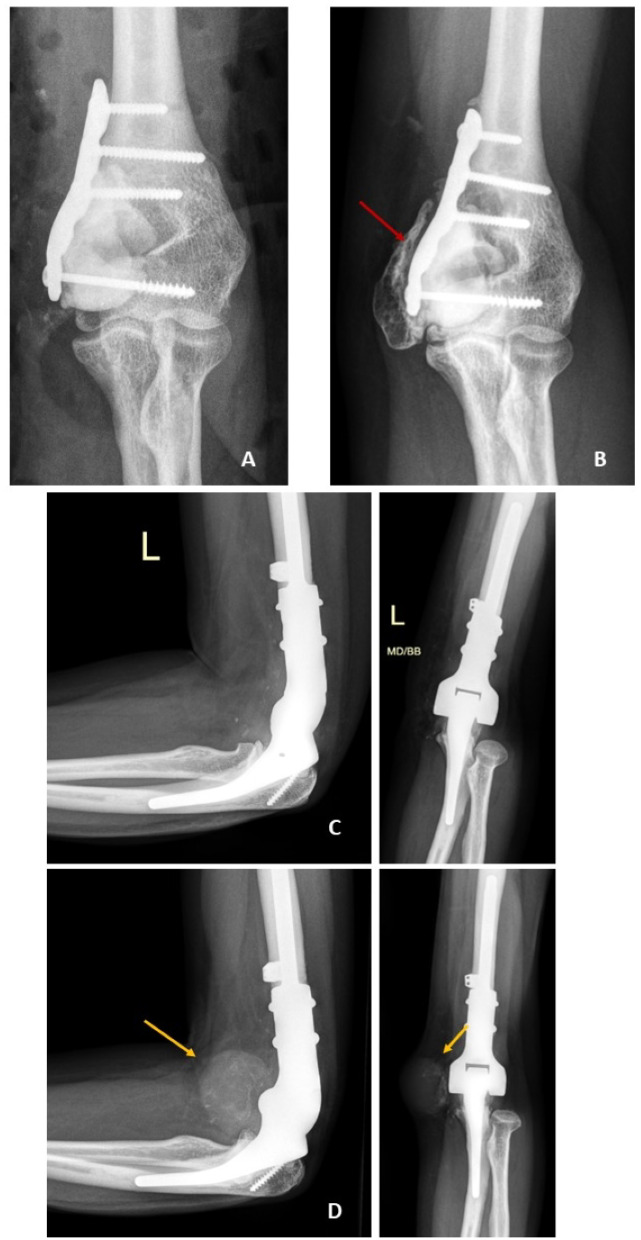

背景:骨巨细胞瘤(GCTB)的诊断和治疗方式的进步引入了分子和放射学工具来改进临床决策。H3.3 G34W免疫组化染色已成为常规诊断标志物,而H3F3A突变分析增强了对预后的认识。治疗主要包括手术方法,如刮除或整体切除,在高风险或不能手术的病例中,denosumab作为辅助。方法:回顾性分析55例GCTB患者的临床病理和影像学表现。采用Campanacci分级系统对肿瘤进行评估。采用H3.3 G34W抗体免疫组化分析和下一代测序(NGS)检测H3F3A突变。对接受denosumab治疗的9例患者的亚组进行进一步的临床结果和组织学变化分析。结果:该队列的平均年龄为37.7岁,肿瘤最常影响膝关节(55%)。所有检测的肿瘤均显示H3.3 G34W阳性染色,其中8个肿瘤显示H3F3A G34W突变。刮除术后复发率为32%,整体切除后复发率为18%。Denosumab治疗平均14.6个月,促进肿瘤缩小和新骨形成,无主要副作用。组织学上,治疗后的肿瘤显示巨细胞耗竭和骨基质沉积增加。结论:手术仍然是GCTB治疗的基石,根据肿瘤特征进行刮除或切除。Denosumab在高风险病例中提供了有价值的辅助手段,提高了手术的可行性并促进了关节的保护。Campanacci分级系统仍然是预测和治疗计划的重要工具,特别是在分子和放射诊断的补充下。未来的研究应侧重于将先进成像技术与人工智能技术相结合,实现GCTB的个性化管理。证据等级:四级。

Results: The cohort had a mean age of 37.7 years, with tumors most commonly affecting the knee joint (55%). All tested tumors demonstrated positive H3.3 G34W staining, with eight exhibiting H3F3A G34W mutations. Recurrence rates were 32% following curettage and 18% after en bloc resection. Denosumab treatment, administered for an average of 14.6 months, facilitated tumor downsizing and new bone formation without major side effects. Histologically, treated tumors showed a depletion of giant cells and increased bone matrix deposition.